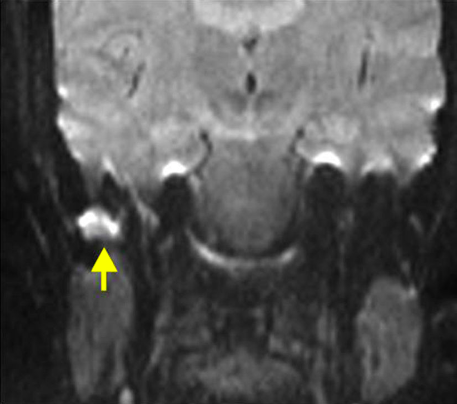

T1 y T2 en otitis media:

• T1: masa hipointensa

• T2: hiperintensa en oído y mastoides

¿Para qué se usa la MRI?

Extensión intracraneal

➞Meningitis

➞Abscesos por complicación

Hallazgos de T2 en mastoiditis complicada:

• Señal aumentada

• Disminución de señal en seno sigmoideo

• Capta contraste